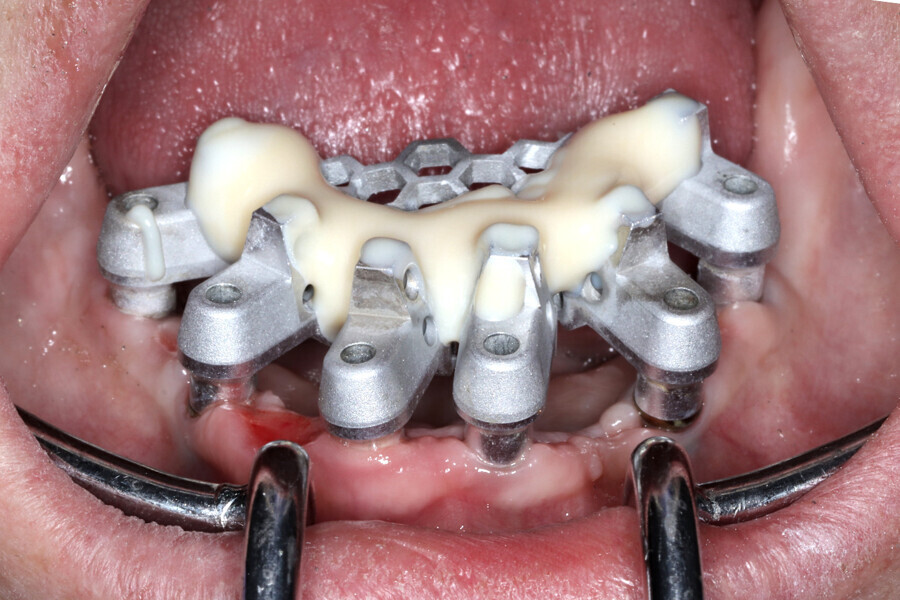

The analogue–digital process utilises MUA-compatible scan bodies (OptiSplint) designed to incorporate an aluminium mesh frame (Fig. 3a) that can be customised chairside (with the snipping tool included) as required by the intra-oral location of the implants. This mesh frame comes in small and large sizes to accommodate various mouth sizes and MUA–implant positions. The workflow involves inserting the scan bodies on to the MUAs intra-orally (Fig. 3b). The proprietary scan bodies have extensions (Fig. 4) to allow the mesh to seat and rotate in close proximity to the extensions, which facilitate luting using a resin base material (STELLAR DC Acrylic, Taub Products). The structure can then be digitised by scanning intra-orally with an intra-oral scanner and extra-orally with an intra-oral scanner or desktop scanner. The bonded splinting of the scan bodies to the mesh frame allows for a simple uninterrupted scan path.

Fig. 3b: Completed Grammetry intra-oral structure secured to MUAs with conventional screws.

The data collected was sent through a scanning software portal (Medit Scan for Clinics) to the dental laboratory with requested changes for correction of the desired smile design. Utilising advanced planning features in the design software (exocad), the midline and tooth size changes were corrected. 3D-printed maxillary and mandibular PMMA restorations were used for try-in using the direct-to-MUA screws (Vortex LA VIS; Fig. 16a). Fit, phonetics, aesthetics and occlusion were evaluated and confirmed using digital articulation (OccluSense; Fig. 16b). The patient was extremely satisfied with the printed try-ins. Since no adjustments were required, the patient was allowed to leave with the printed try-ins as new provisional restorations made from extra-strong resin. The new provisional restorations were worn for ten days to confirm form and function. The final shade was chosen, and metal-free monolithic zirconia restorations were then fabricated by the laboratory.